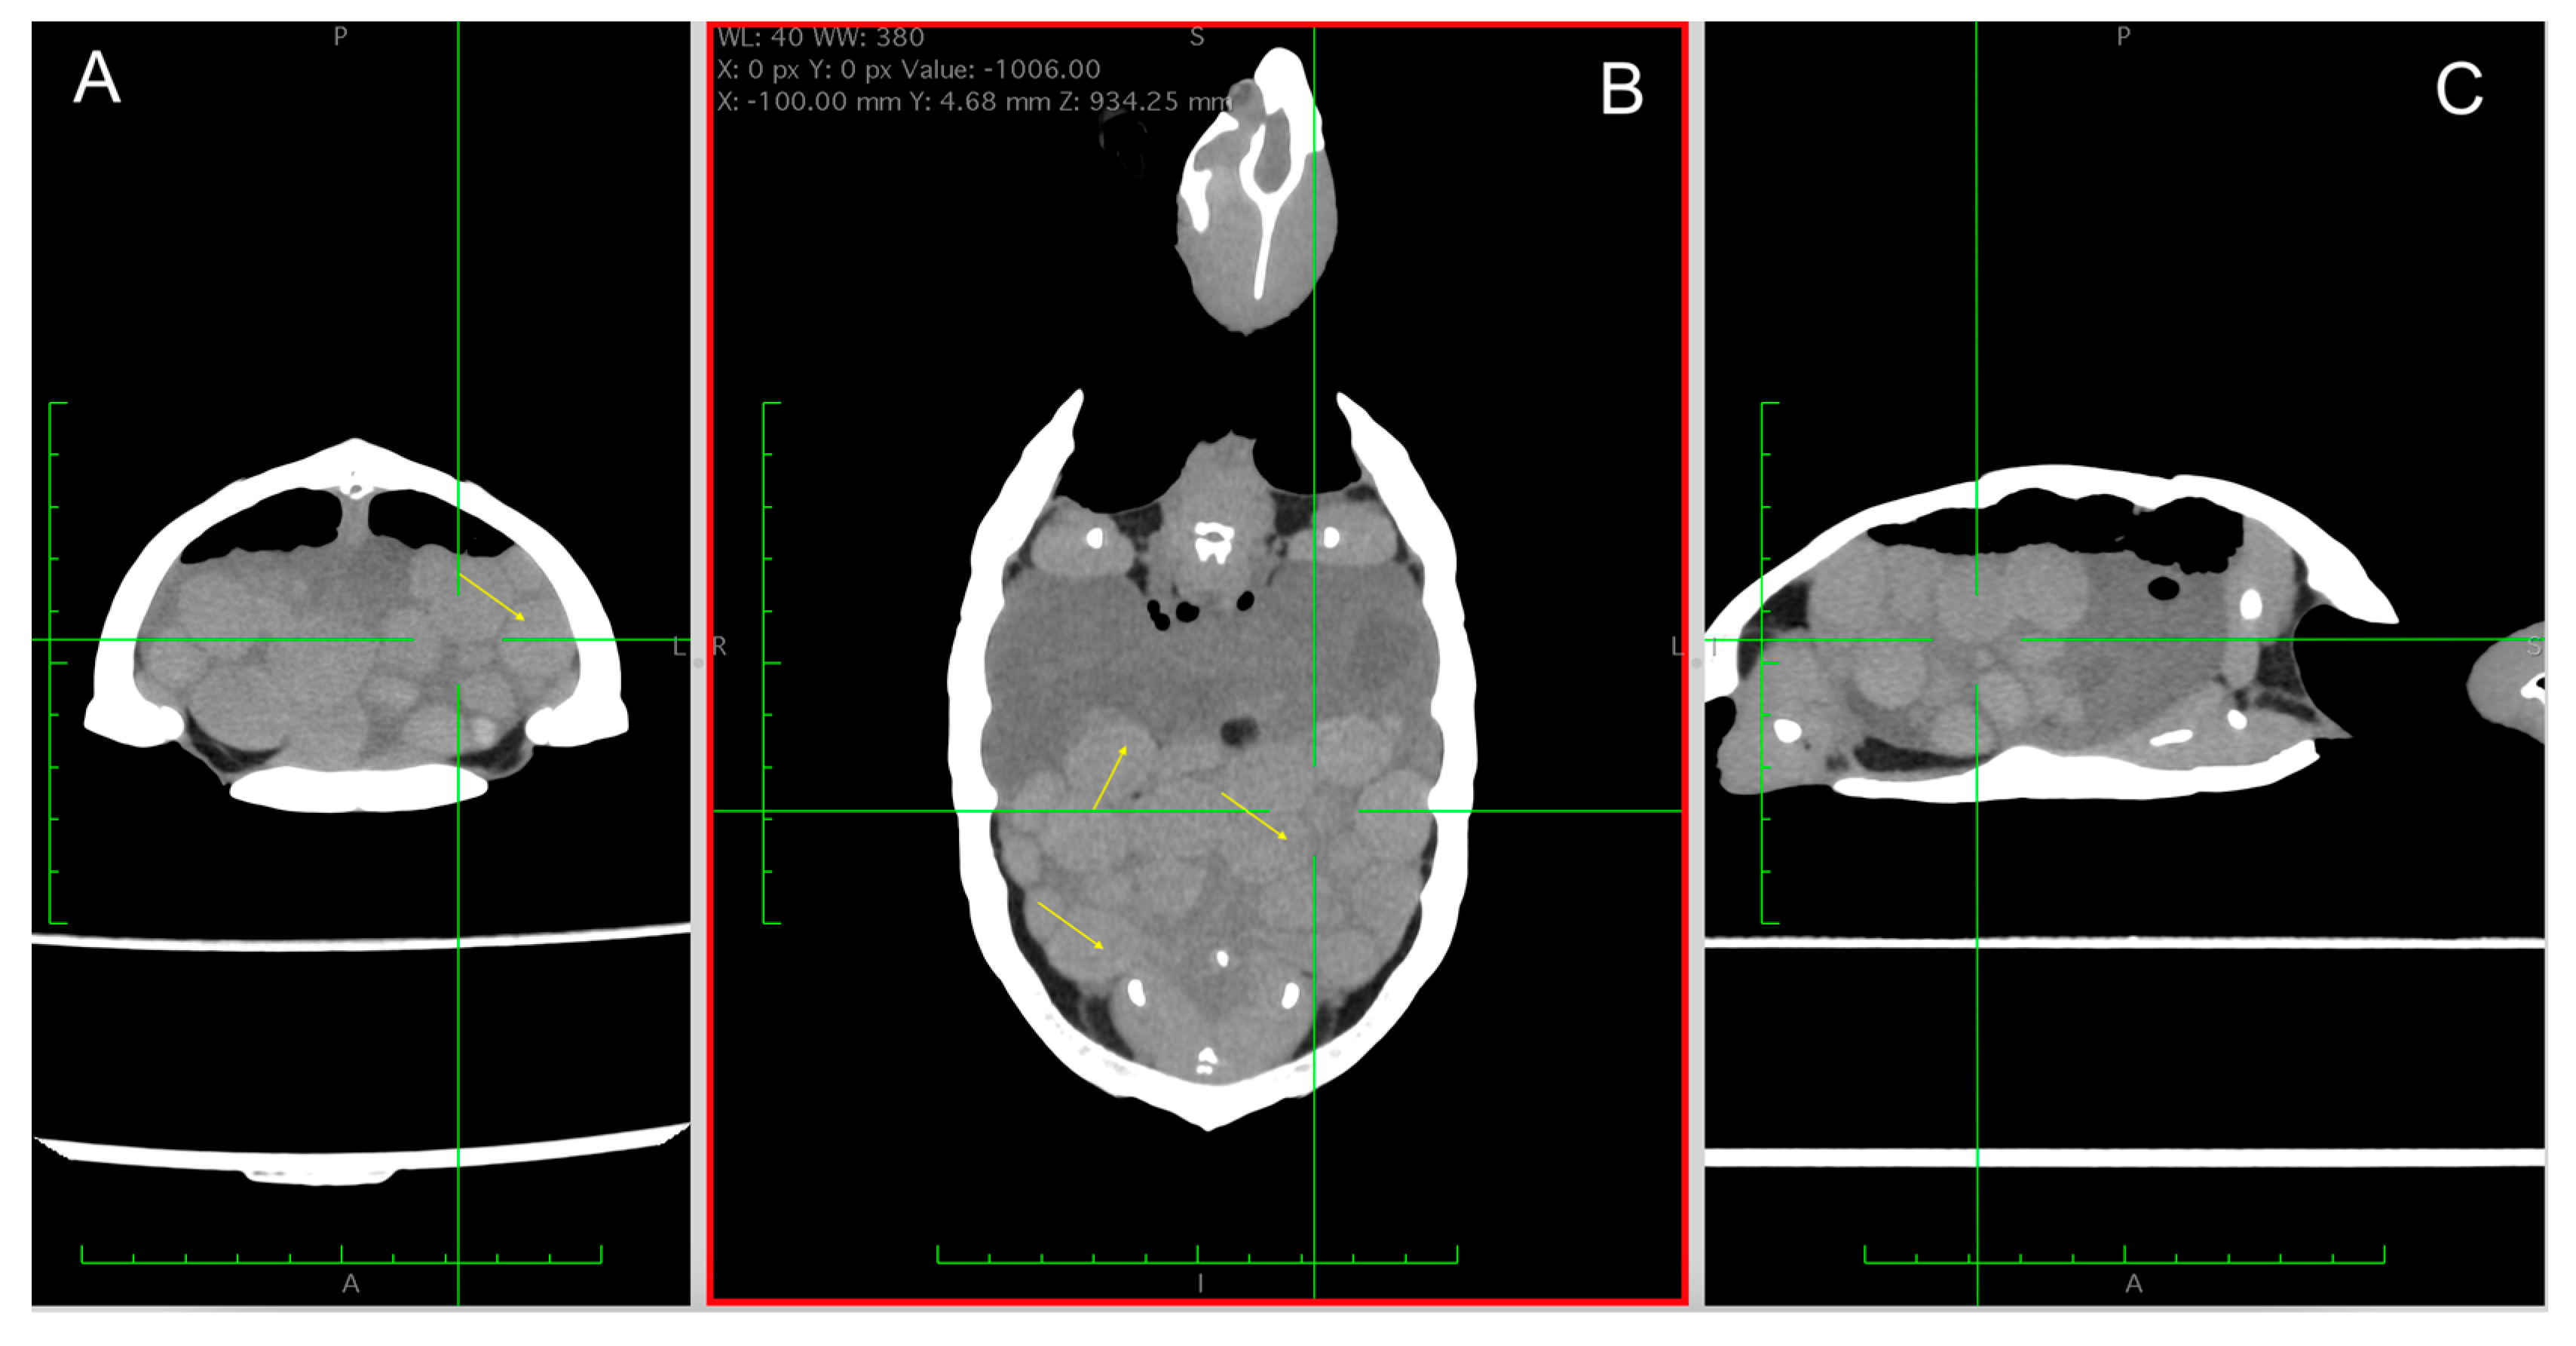

5.5. CT Scan